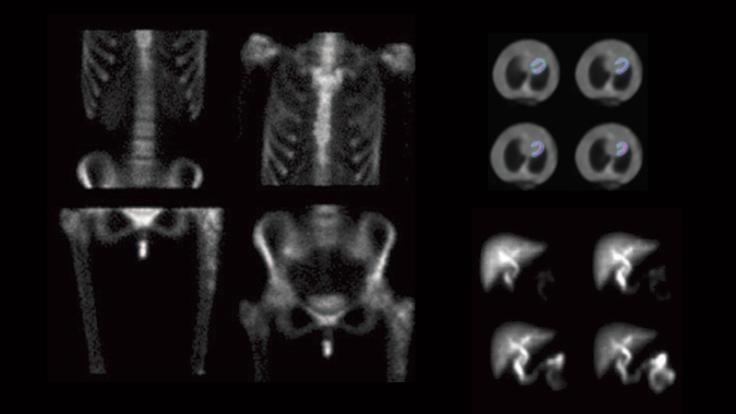

Making the portable gamma camera

The end of the Cold War and the cancellation of the Superconducting Super Collider led to the creation of a life-saving medical device.

Detectors in daily life

Not only are particle detectors essential to making discoveries in particle physics, they also play important roles in industry, science and medicine.